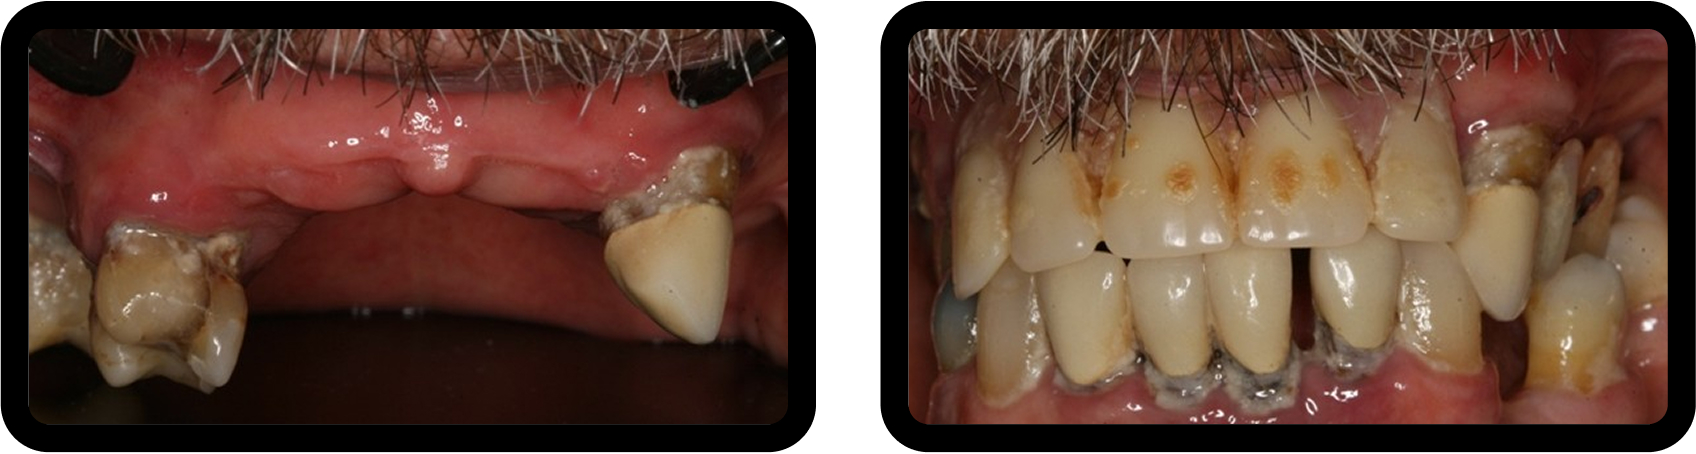

After radiographic analysis, periodontal assessment, and occlusal examination, Jerry presented with failing maxillary dentition supported by a removable partial denture, significant occlusal collapse, and esthetic dissatisfaction, all of which negatively affected his confidence at work (Fig. 1).

His occlusal collapse included uneven wear and super-eruption of the left maxillary cuspid, contributing to his functional and esthetic concerns (Fig. 2).